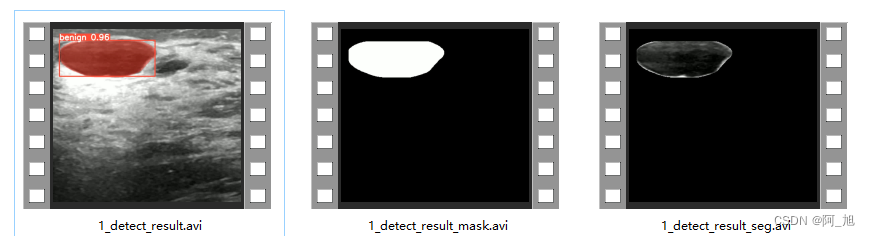

2.点击保存按钮,会对视频检测结果进行保存,同样会保存3种类型结果,分别是:检测分割结果标识视频、分割Mask视频以及原视频分割后的视频,存储路径为:save_data目录下。

视频检测演示:

视频保存演示:

视频检测保存结果如下: